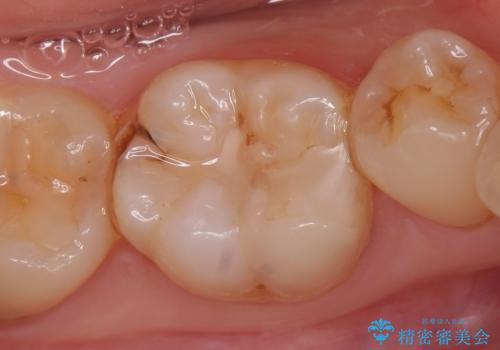

- 右下6番目の歯がしみるといらっしゃった方の症例です。

古い樹脂及び虫歯を除去後、セラミックインレーにて修復を行いました。